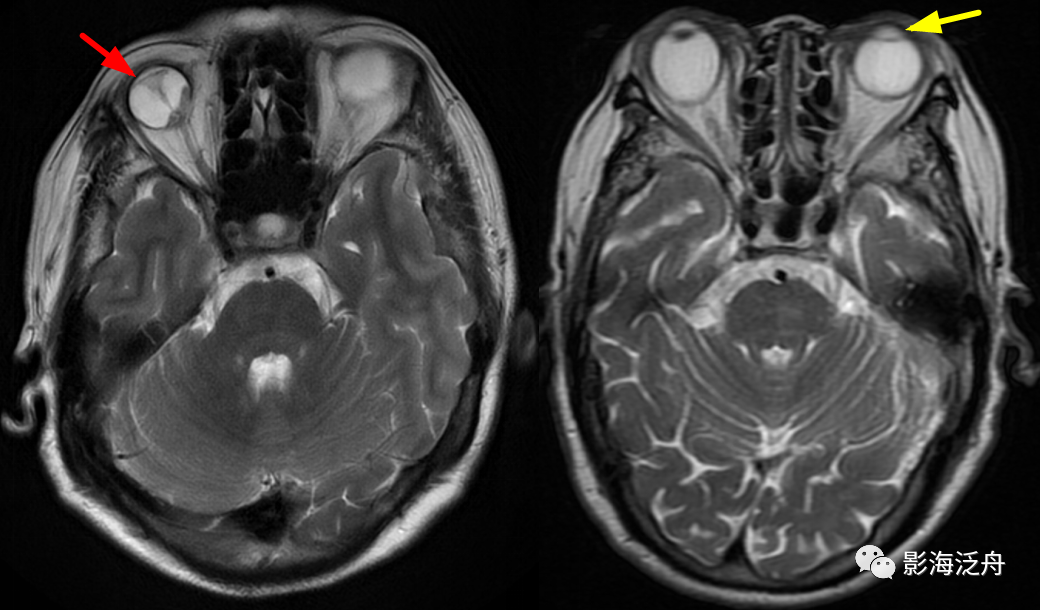

右侧为视网膜剥脱(红箭),眼球后部为剥离的视网膜组织及积血区;左侧为白内障患者,T2WI上患眼晶状体信号均匀增高为其特征性表现。